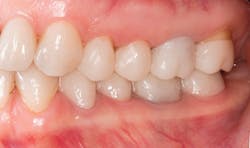

Esthetic functional prototypes have been utilized to test drive the proposed smile design, vertical dimension, phased treatment plan, and functional blueprint for future care.3–5 Different materials and techniques have been used to create bonded functional prototypes, such as polymethyl methacrylate (PMMA) and highly filled flowable composites.6–9

A patient presented with multiple deficient restorations, discolored teeth, and attrition (figures 1–4). The patient’s treatment plan was a full-mouth rehabilitation with a combination of veneers, crowns, and onlays.

Esthetic and functional prototypes are an effective way to evaluate esthetics and function of a proposed restorative plan, all while spreading the cost of definitive treatment over time. Esthetic, functional, and long-lasting restorations can be achieved if clinical and laboratory protocols are carefully followed using adhesive additive techniques.